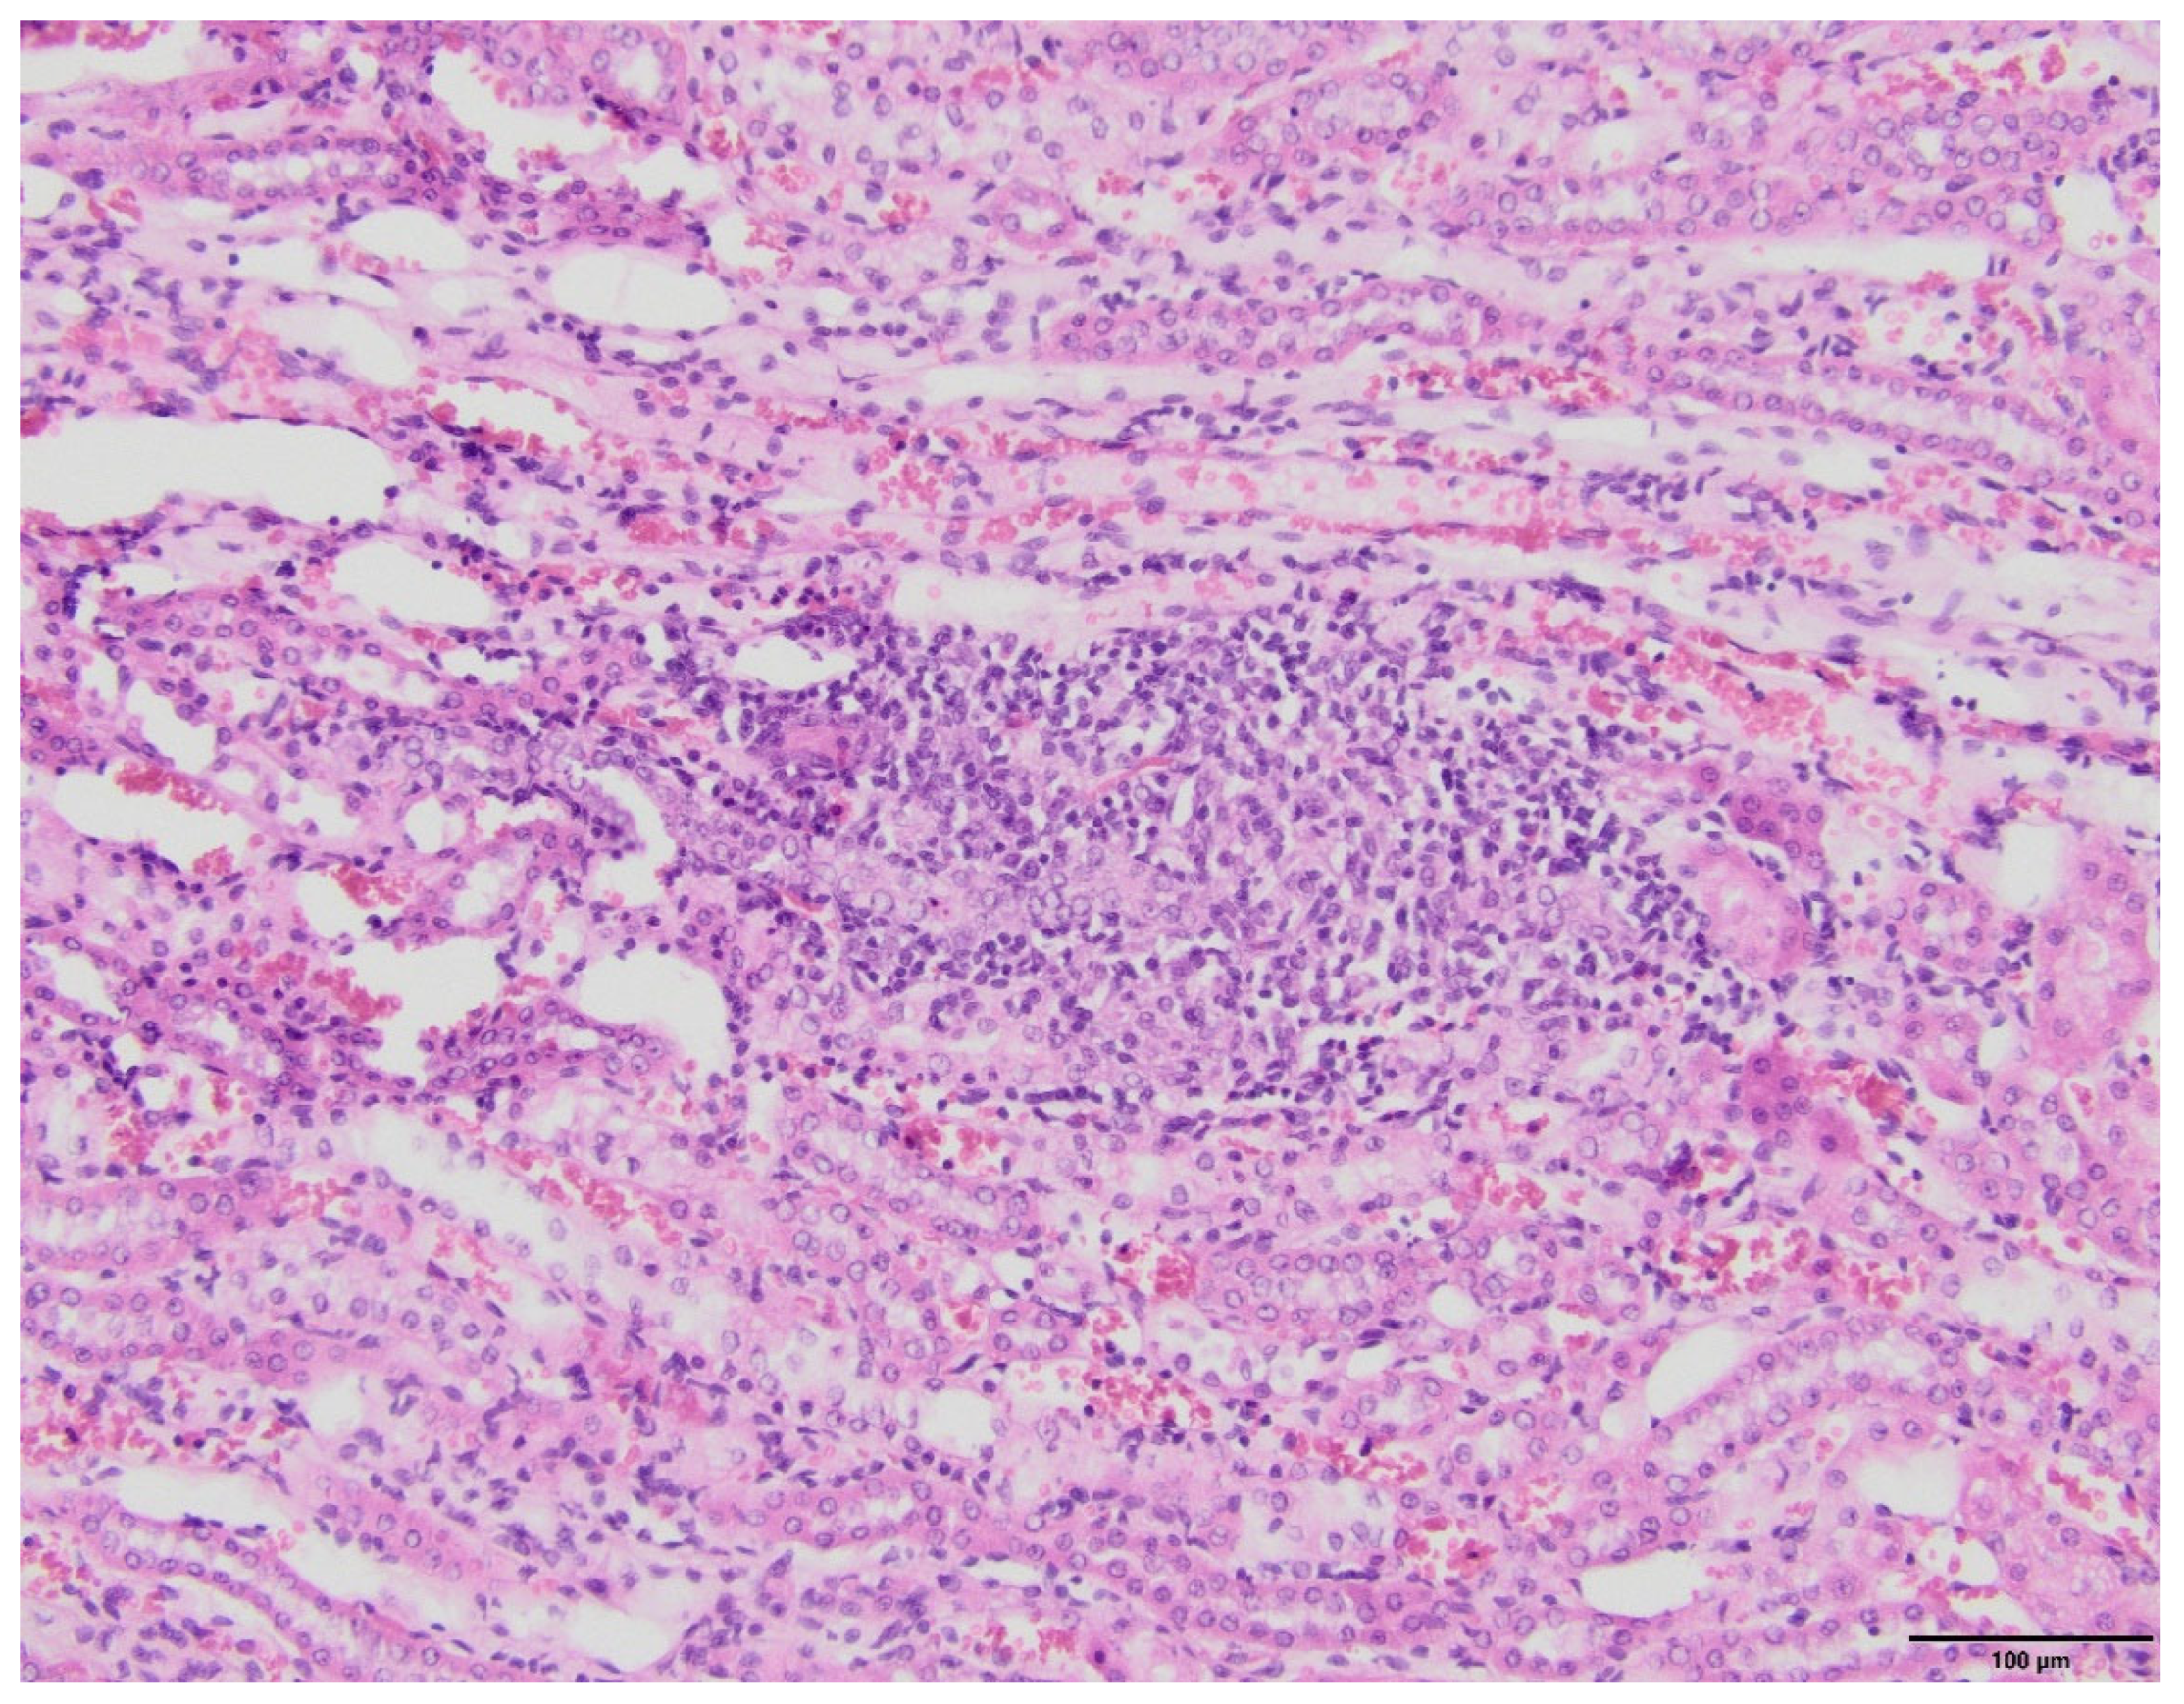

2.4. Kidney Histopathology